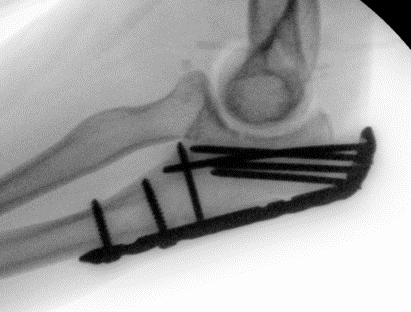

ORIF with olecranon plate

Indication

Fracture distal to center of rotation of elbow / trochlea

Technique

Lateral decubitus with tourniquet

- curvilinear incision to avoid prominence of olecranon

- identify and protect ulna nerve

- reduce fracture with arm in extension

- ensure articular congruity

- use anatomical precontoured plate

- may want to split distal triceps to reduce proximal plate prominence